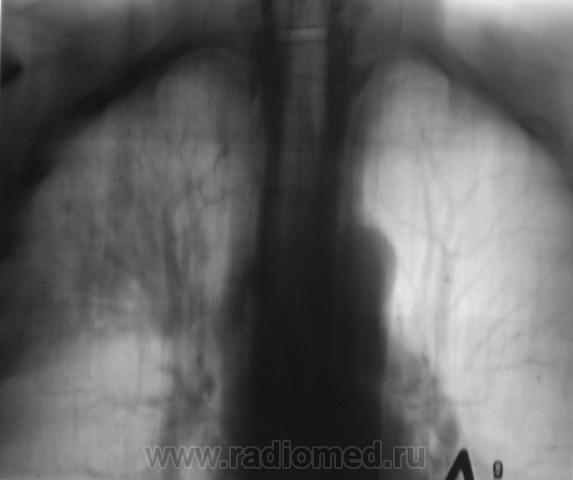

Пациент, при расшифровке флюорограмм, "взят на контроль". Произведено стандартное рентгенологическое исследование. Вот рентгенограмма.

Томограммы.

Ваше мнение уважаемые коллеги?